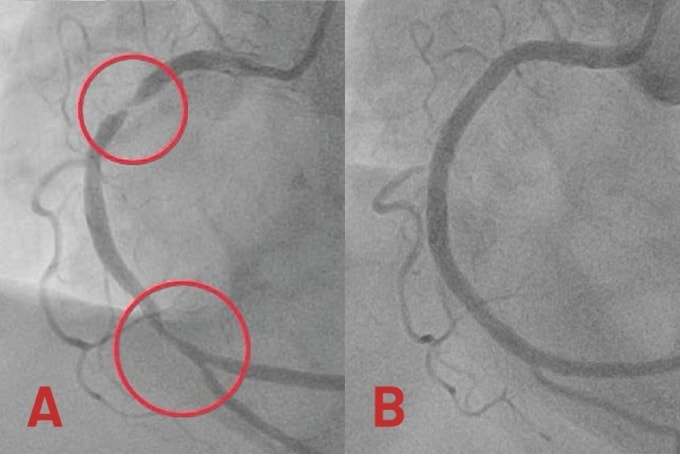

Động mạch vành phải người bệnh bị hẹp khít đến 99% đoạn giữa và hẹp 80-90% đoạn xa. Êkíp luồn dây dẫn từ động mạch quay (ở cổ tay) đi qua vị trí hẹp nghẽn nặng để nong rộng mạch máu, mở đường cho việc đưa stent vào tái thông mạch vành. Sau gần một giờ, bác sĩ đặt thành công hai stent phủ thuốc tại hai vị trí hẹp nặng, khơi thông con đường đưa máu từ động mạch vành phải đến nuôi tim.